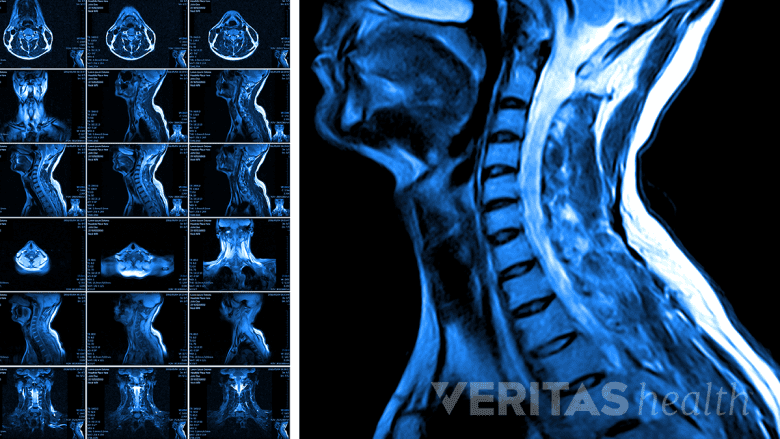

An MRI scan is a useful imaging tool to diagnose central canal stenosis.

The first line medical imaging technique used to assess the location and severity of stenosis of the spine is a magnetic resonance imaging (MRI) test. If the MRI is inconclusive or not possible, a computed tomography (CT) scan may be done.

MRI for central canal stenosis

An MRI of the spine shows detailed images of soft tissues, length of the spinal canal, the cross-sectional area of the central canal, and any other changes in the surrounding structures. However, standard MRI’s may have some limitations in detecting the severity of certain types of stenosis, such as lumbar stenosis.